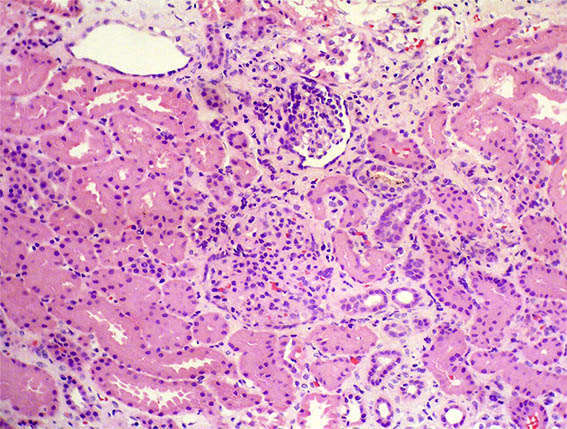

Con diagnóstico de síndrome nefrótico, se hace biopsia renal. Observe las imágenes.

Figura 1. H&E, X200.